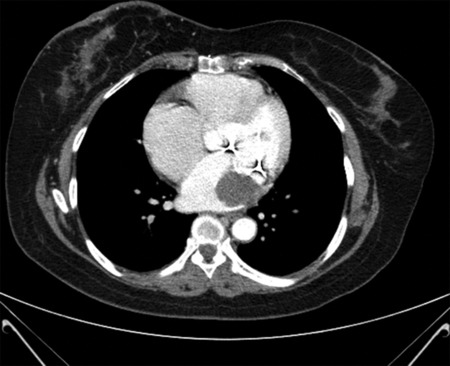

A 54-year-old patient with a medical history of hypertension, dyslipidemia, and diabetes underwent mitral valve replacement surgery with a biologic valve. During a chest computed tomography scan for breast neoplasia staging, a reduced luminal filling in the left atrium (3.6 cm) was unexpectedly found, prompting further cardiac evaluation. The patient was referred to the emergency department experiencing shortness of breath and fatigue, which improved after furosemide administration, and remaining stable throughout hospitalization. A transesophageal echocardiogram was performed the following day and revealed a biologic mitral valve prosthesis slightly displaced toward the left ventricle with an average transprosthetic gradient of 7 mmHg. Notably, a sizable intermediate echogenic mass measuring 3.0 cm × 3.5 cm was detected and attached to the prosthesis ring in a lateral and posterior position, within the left atrium. A mild degree of periprosthetic regurgitation was also noted. Given the substantial suspicion that the observed mass was a thrombus, the patient was commenced on anticoagulation therapy while awaiting cardiac magnetic resonance imaging for better characterization of the mass. Over 4 weeks, the thrombus notably decreased in size, disappearing entirely by the 6th week. This case highlights the significance of employing multiple imaging techniques in managing cardiac masses. The incidental discovery of the mass, its characterization, and subsequent management through anticoagulation, followed by confirmation and monitoring through echocardiogram, underscore the importance of a multimodal approach in diagnosing and treating such conditions.